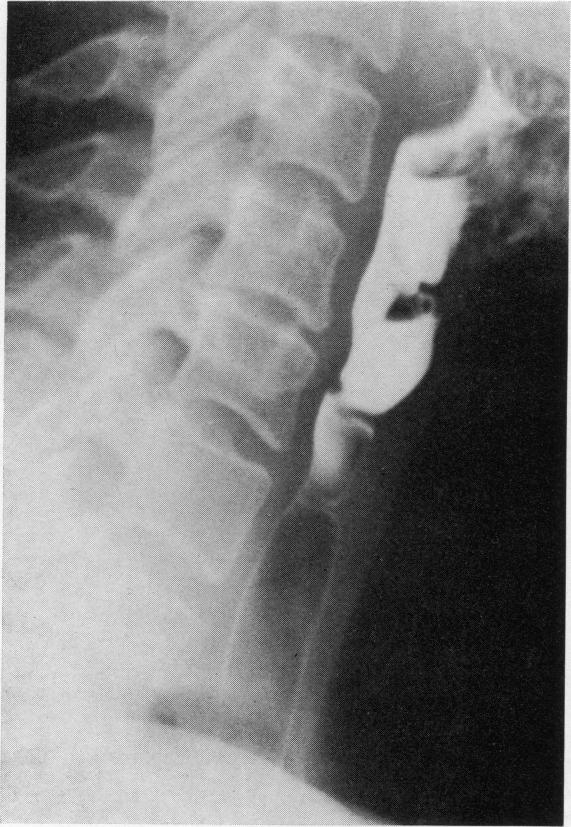

The anatomical variations of the Plummer-Vinson stricture in the cervical oesophagus. An X-ray atlas.

Ulster Med J. 1978;47 Suppl 2(Suppl 2):15-59.